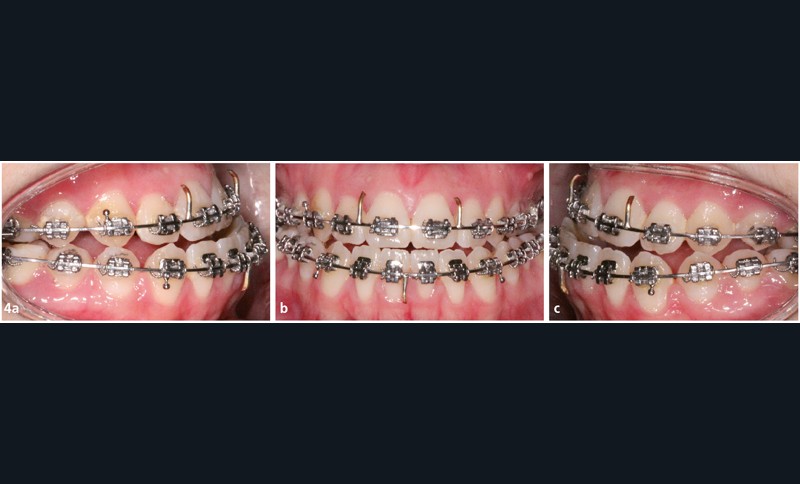

Traitement multi-attaches (fig. 4, 5, 6 et 7)

Les extractions orthodontiques ont été réalisées avant le collage de l’appareillage multi-attache Roth 022x.028.

Une séquence d’arcs Niti (.014, .018, .018x.025) a permis de réaliser l’alignement et le nivellement de l’arcade mandibulaire, avant de passer en acier (.019x.025).

La séquence d’arcs a été différente au maxillaire : un acier .014 en by-pass sur les incisives latérales a dans un premier temps été mis en place afin d’éviter tout effet néfaste de vestibuloversion.

Ensuite un arc avec des boucles de fermeture acier .018 a été utilisé afin de permettre le rabitting compte tenu de l’encombrement majeur.

Une fois les espaces d’extractions fermés, nous avons poursuivi le nivellement avec des arcs aciers .016x.022 puis .018x.025 afin de programmer la chirurgie orthognathique.